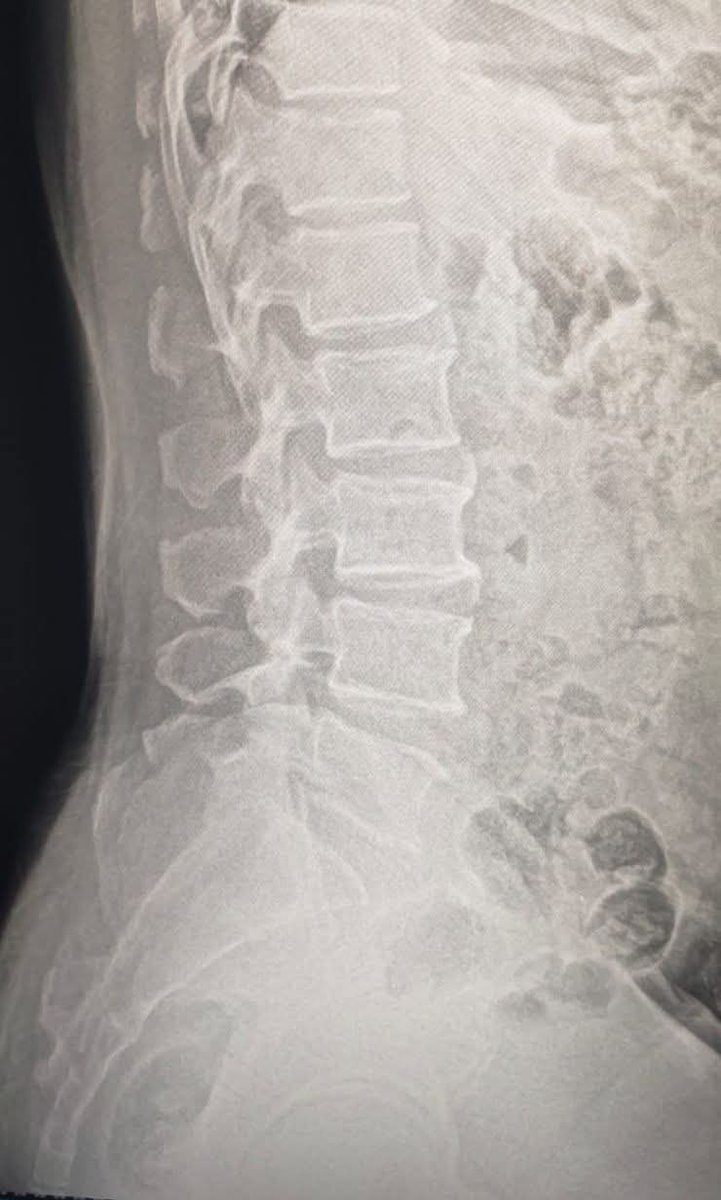

What fracture type is this? Look closely at the vertebral body—can you identify the pattern of compression and fragmentation? Drop your answer below 👇 and see if you caught this classic injury. Read: tinyurl.com/3mbmvy2b #orthopedics #radiology #xray #mededucation

MedEd_Cases's tweet image. What fracture type is this?

Look closely at the vertebral body—can you identify the pattern of compression and fragmentation? Drop your answer below 👇 and see if you caught this classic injury.

Read: tinyurl.com/3mbmvy2b

#orthopedics #radiology #xray #mededucation